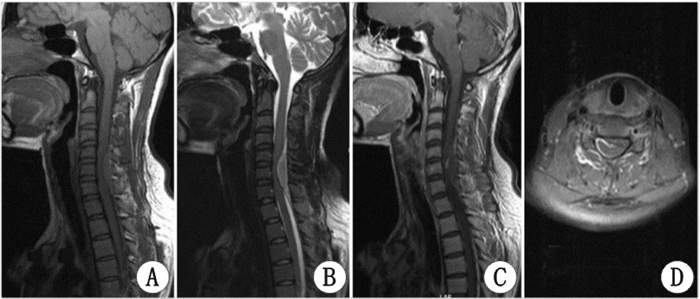

| 女性,27岁,肢体麻木无力伴小便失禁10h,入院查体:乳头平面以下躯体及右上肢浅感觉减退,双下肢肌力0级,腱反射亢进,双侧巴氏征阳性。颈椎JOA评分5分。颈椎MR:颈5~7椎管后方硬脊膜外占位,图A示矢状位T1加权像占位为等信号,图B示矢状位T2加权像占位为高信号的外周和低信号的血肿中心。图C及D示增强后的矢状位及横断位MR图像 图 1 急性硬脊膜外血肿术前MRI Fig 1 A case of MRI in acute spinal epidural hematoma |

3.3 影像与诊断急性起病的患者病情进展迅速,早期诊断主要依靠CT及MRI。脊椎CT主要表现为椎管内占位性病变,占位呈高密度影,矢状位呈梭形、边界清楚,硬膜囊明显受压变形。MR能更加清晰地显示椎管内占位的部位、范围及与脊髓、硬脊膜的关系。急性期的出血(<3 d)在T1WI为等或稍高或混杂的信号[11],在T2WI为高信号影的外周和低信号的血肿中心[12]。进入亚急性期后(出血后3~14 d),T1及T2加权在信号上均逐渐增高,在亚急性末期,因为含铁血黄素的沉积,外周开始出现低信号[11]。Groen和Van Alphen[13]统计文献报道330例SEDH发病部位以颈胸部及胸腰部最为常见,约占77%,且血肿多位于椎管后方,脊髓的背侧。这可能是因为硬脊膜腹侧与椎体贴近,相对活动少,不易形成血肿。